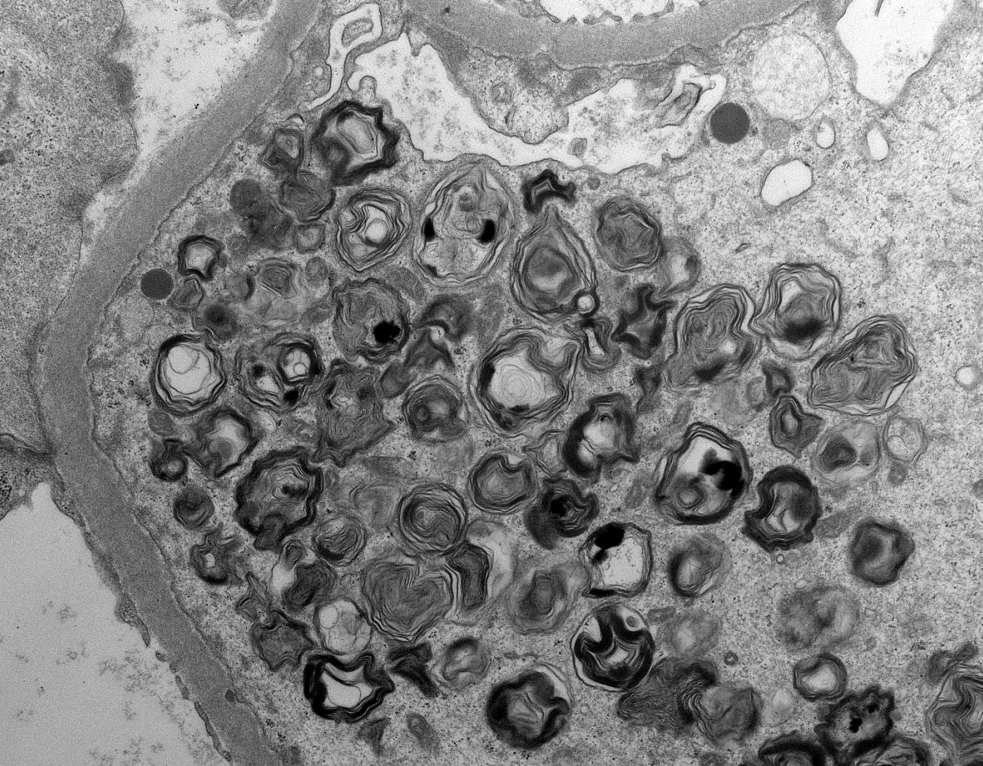

Mini case-series of crystal-storing histiocytosis (CSH) affecting predominantly glomerular loops with detailed literature review of renal CSH, images of one of the cases are depicted below, authors.elsevier.com/c/1Zh4S3uV~y8B…